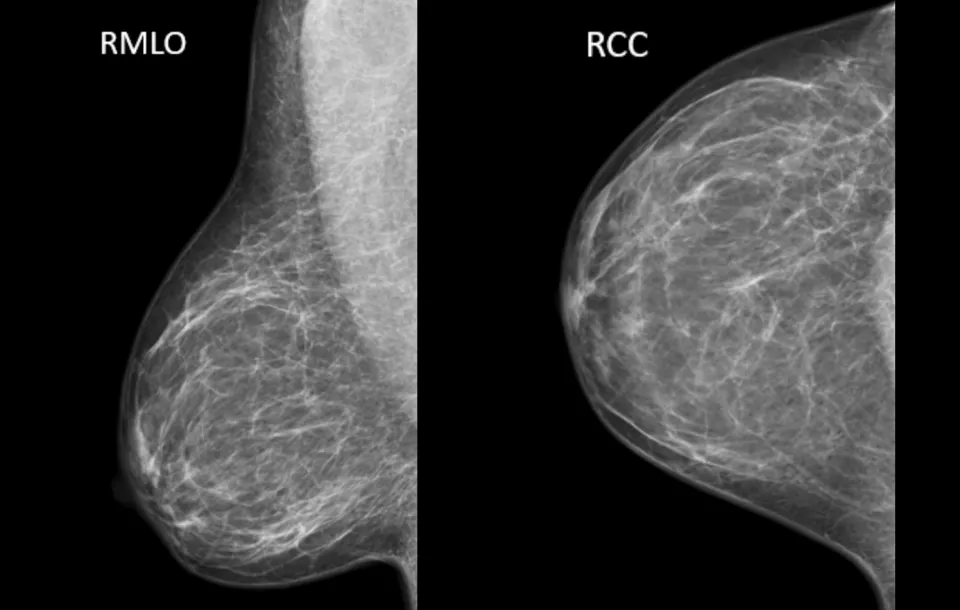

- Understand what breast tissue is visualized on the CC and MLO view

- Identify quality and sub-quality aspects of an image

- MLO View

- Proper demonstration of pectoral muscle

- Drooping tissue

- Proper demonstration of IMF

- Skin folds

- Film Critique

- Drooping breast

- Muscle shape and length

- Nipple in profile